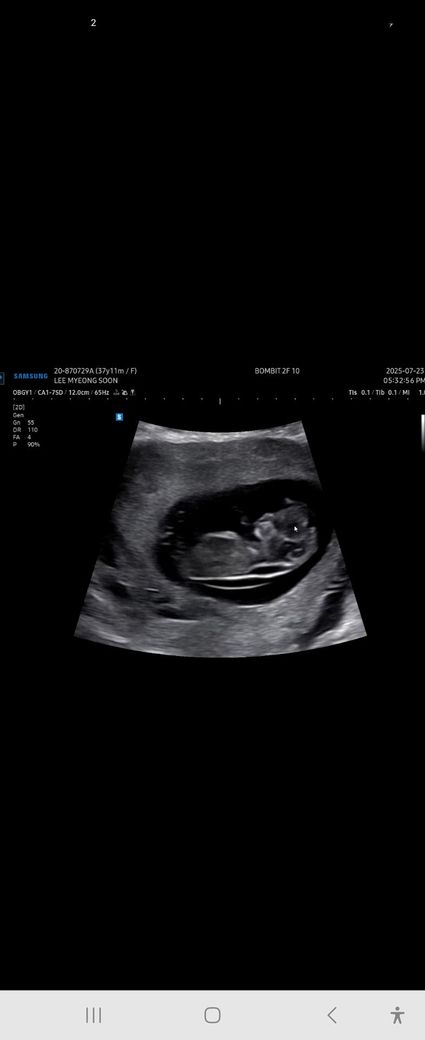

10주차 초음파인데 아기는11주크기라고하셨구요

집에와서보니 목투명대가 두꺼워보이는데 괜찮은걸까요? 노산이고 걱정되서 올려봅니다 답변 부탁드려요

현재 사진만으로는 목투명대의 두께를 정확히 알기는 어렵고 보통 10주~11주 아기의 경우 목투명대가 3mm 이하일 시 정상적인 소견이기 때문에 검사하신 산부인과에서 해당 길이가 어느 정도인지 구체적으로 확인해 보시는 것이 이상 여부를 확인하는데 도움이 될 것으로 사료됩니다.